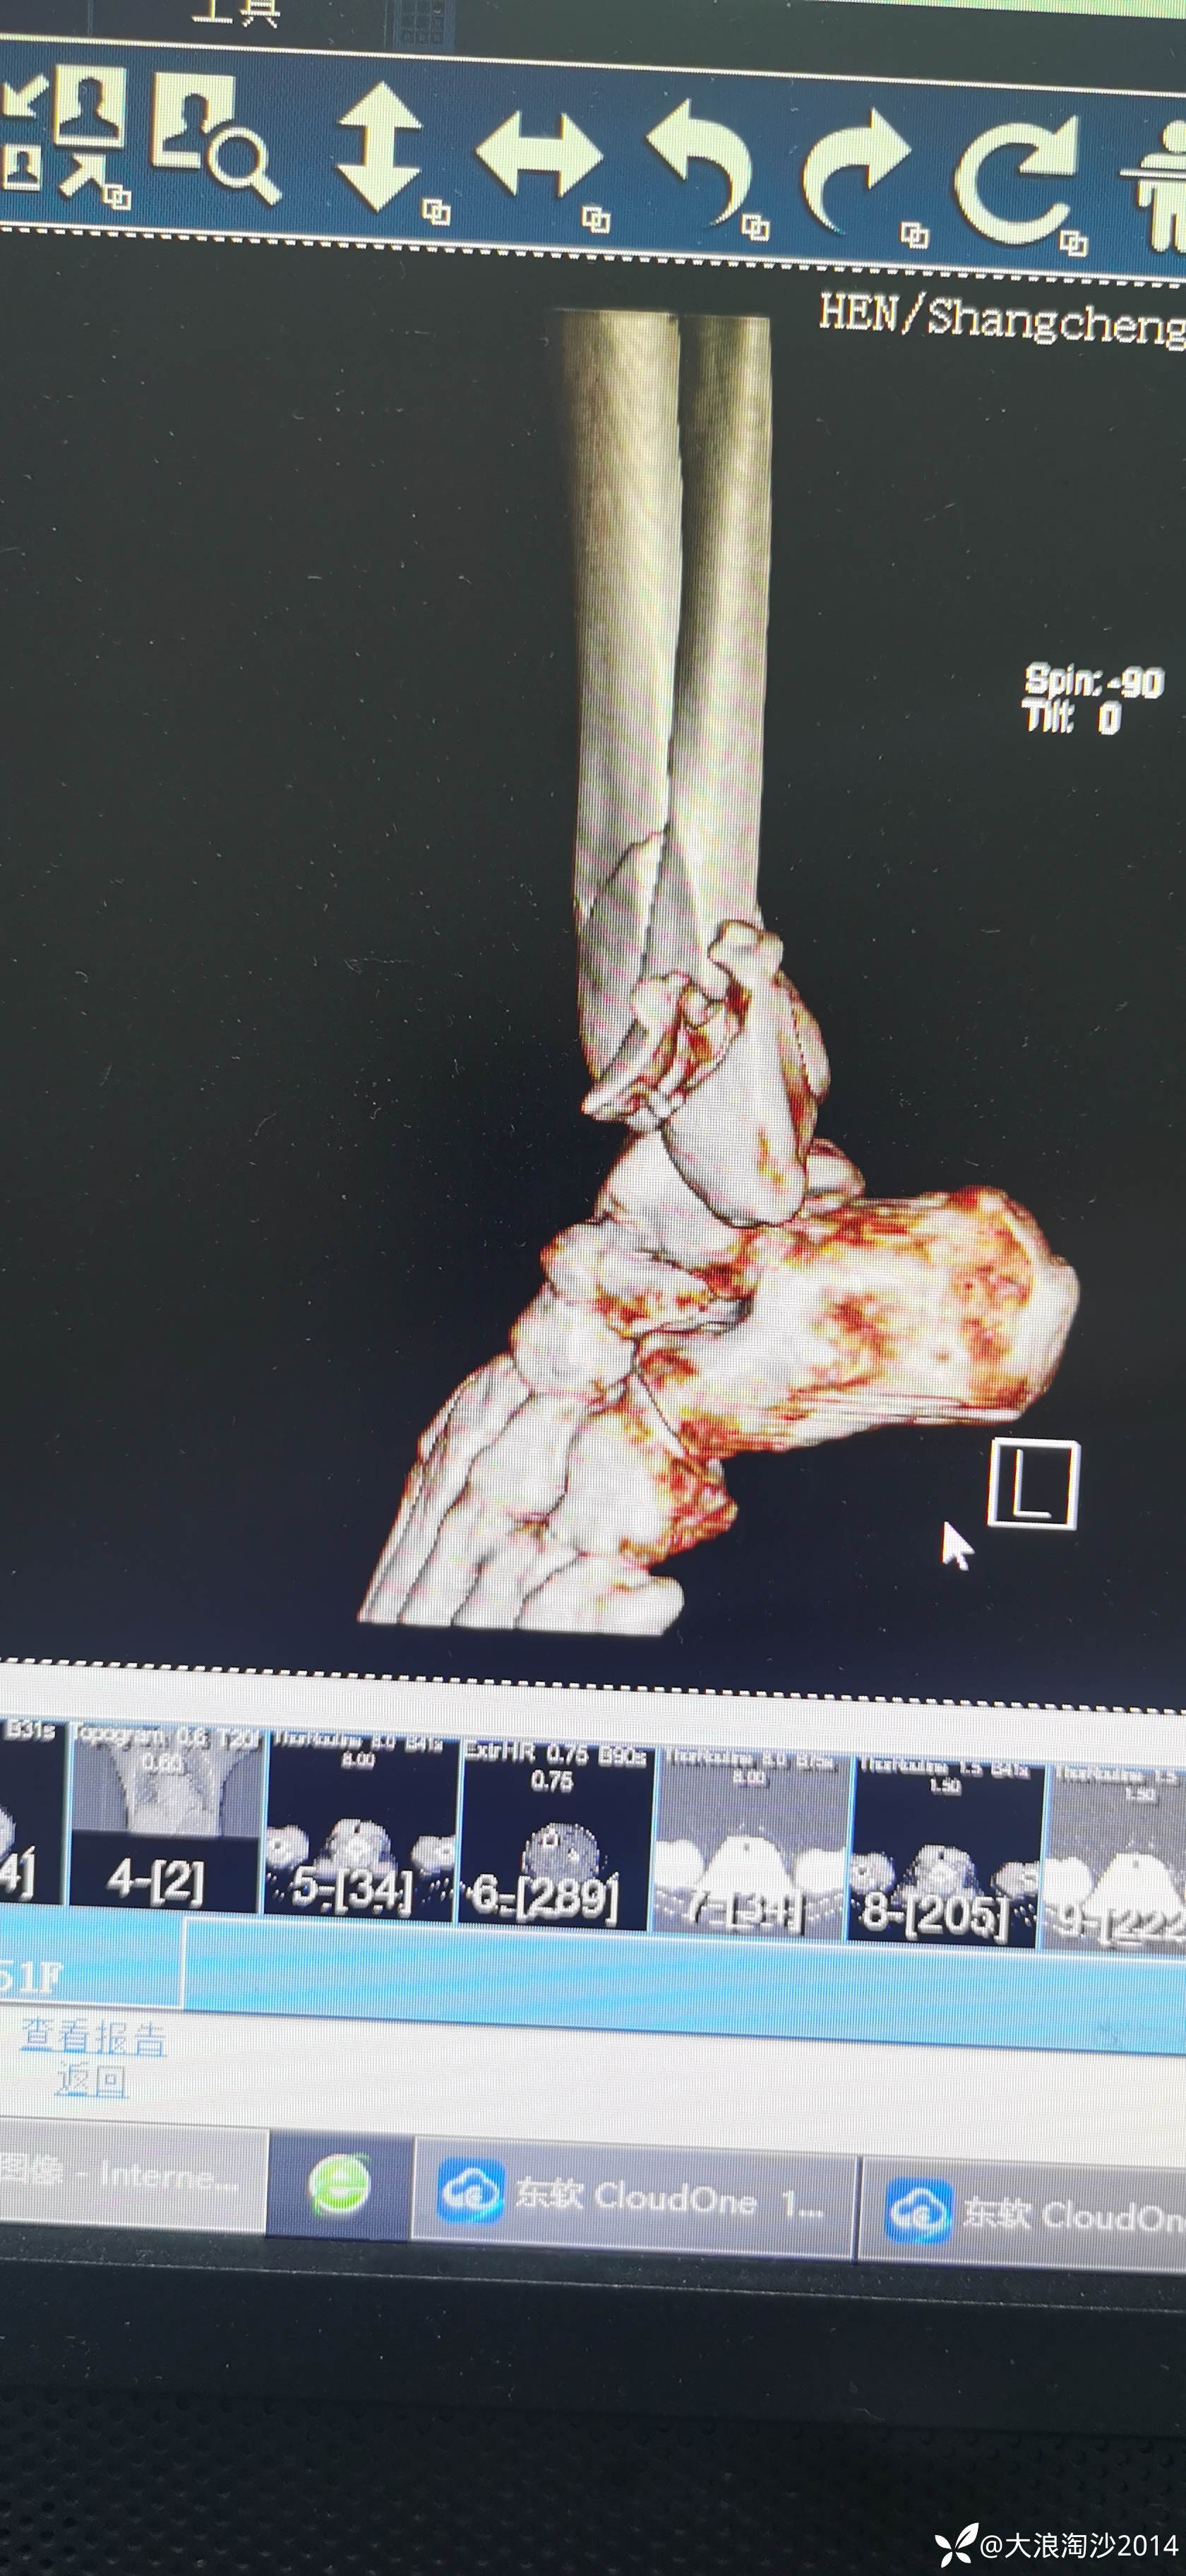

一65岁女性患者,偏瘦,体重75斤,车祸外伤致左胫腓骨远端骨折,入院后消肿后,病人可以用皮包骨头形容,考虑胫骨远折端不适合用内侧插板(mippo技术),病人太瘦,如取两个切口分别处理胫腓骨,切口容易出现问题,因此采用前外侧一个切口处理胫腓骨远端骨折(片子顺序上传有点乱)